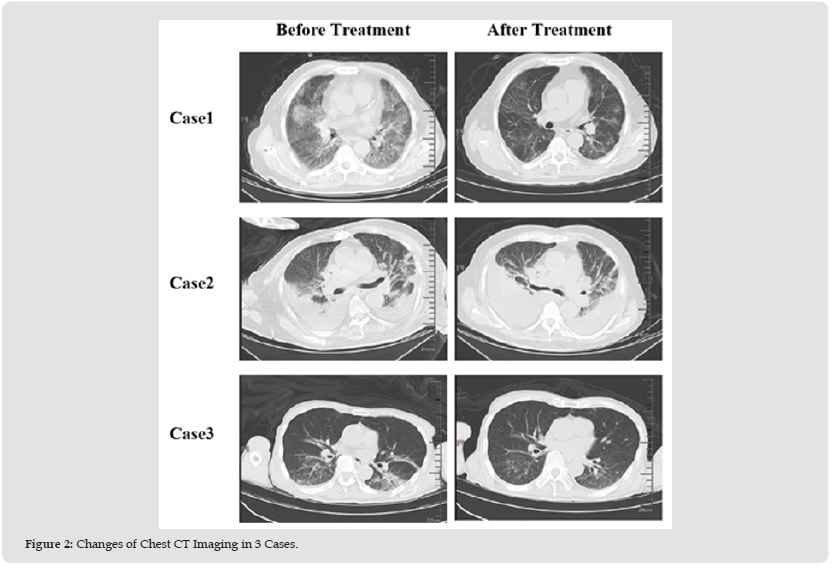

In this study, we screened out ordinary plasma containing high levels of IgG antibody and applied it to 3 patients with severe and critical COVID-19, which could activate passive immunity. The basic clinical characteristics of patients are shown in Table 2. COVID-19 typing standard reference the Diagnosis and Treatment Plan for Novel Coronavirus Infection (Trial Version 10). It is worth mentioning that the 3 patients came from different periods of the epidemic of SARS-CoV-2, which provide a strong evidence for the application of plasma therapy for COVID-19 patients. SARS-CoV-2 antibody or CT values in 3 cases were shown in Tables 3-4. All patients obtained their consent. The Case 1 patient was complicated with lymphoma. After three rounds of anti-COVID-19 therapy, the SARS-CoV-2 Ct values was still low. During the course of treatment, 2800ml of convalescent plasma was infused in combination with immunoglobulin. After treatment, the chest CT lesions were reduced (as shown in Figure 2), and the CT value of SARS-CoV-2 was above 35 for two consecutive times. In Case 2, the patient has the basis of cardiovascular disease, the general condition is weak, and it is complicated with drug-resistant bacteria and fungal infection. The diagnosis of severe COVID-19 is clear, and it does not turn negative after three rounds of antiviral treatment in the early stage, so it is given plasma infusion treatment for 2 weeks in the recovery period, with a daily dose of 400ml. After that, the chest CT shows that the lesion has not progressed (as shown in Figure 2), and the CT value of SARS-CoV-2 turns negative, suggesting that the treatment effect is acceptable. In order to further improve the persuasiveness, we randomly selected an elderly male as Case3. The patient had no basic disease in the past, and applied two rounds of antiviral therapy with small molecular drugs. The CT value of SARS-CoV-2 fluctuated around 20, so plasma treatment was applied for one week without absolute contraindications, with a total infusion of 1400ml. After treatment, the chest CT imaging findings were significantly reduced (Figure 2), the SARS-CoV-2 turned negative, and the general state improved.